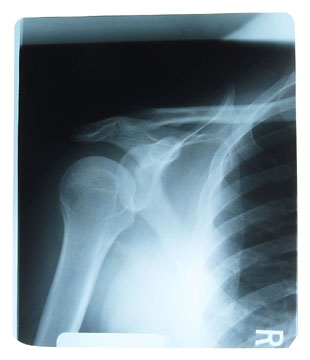

Frozen shoulder or adhesive capsulitisI

Is a condition which affects shoulder joint mobility with stiffness and pain and occurs usually between the ages of 40 and 60. Unaided recovery can be slow and symptoms can last for two to three years.

Diagnosis

The chiropractor will be able to make an accurate diagnosis using orthopaedic and neurological tests and may suggest referral for diagnostic x-rays.